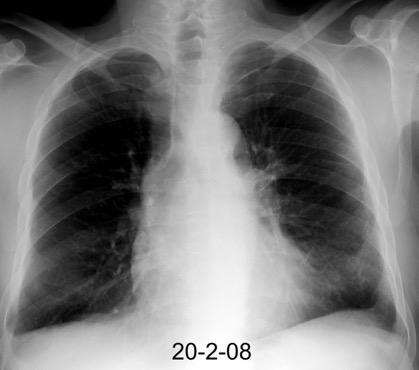

Neumonía a neumococos base izda. con derrame que aumenta.

Broncograma en lateral y en US.

(36-66% en ingresados)